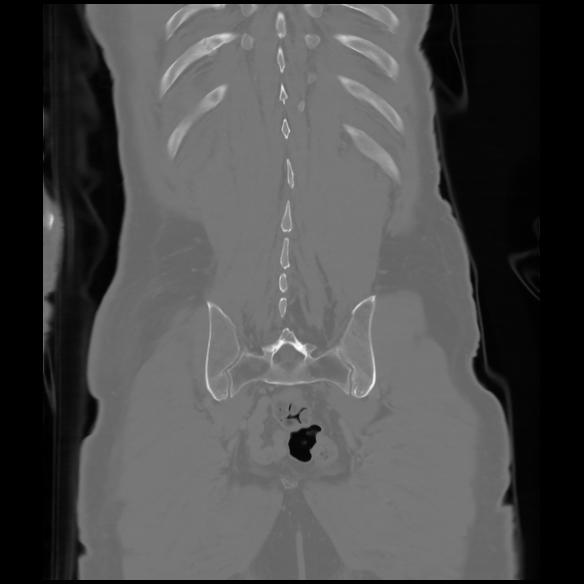

6 CUERPO,CE,Coronal,3.000,CUERPO,Coronal,